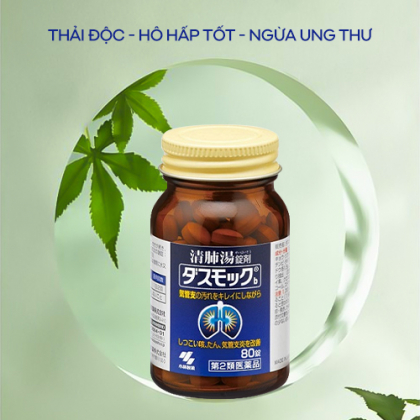

Viên uống Kobayashi giúp hỗ trợ điều trị bệnh phổi

Viên uống bổ phổi Kobayashi Nhật Bản với 16 loại thảo dược quý giúp giảm viêm, tan đờm, bổ phế, hỗ trợ loại bỏ bụi bẩn, vi khuẩn bên trong phổi, củng cố sức khỏe hệ hô hấp.

Công dụng nổi bật của viên uống bổ phổi Kobayashi

- Viên uống được làm từ 16 loại thảo dược quý, giúp xoa dịu và làm lành tổn thương ở phổi do hút thuốc lâu ngày, tiếp xúc với môi trường nhiều bụi bẩn, ô nhiễm, vi khuẩn, virus…

- Hỗ trợ loại bỏ bụi bẩn, thải độc tố tích tụ trong màng phổi.

- Thanh lọc phổi, cải thiện hệ hô hấp, lưu thông khí huyết tốt hơn.

- Tăng cường sức đề kháng, xoa dịu và làm lành các bệnh hô hấp lâu năm.

- Cải thiện tình trạng đau ngực, ho khan, khó thở, mệt mỏi…

- Bảo vệ lá phổi trước những tác nhân tiêu cực từ môi trường bên ngoài như bụi bẩn, ô nhiễm… hay là hút thuốc lâu năm.

- Giảm thiểu nguy cơ mắc bệnh ung thư phổi.